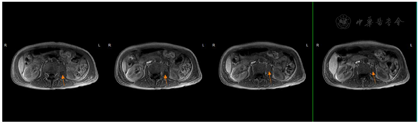

2018年7月2日患者第二次我院住院诊治,此时患者仍有发热,伴额头、左颈部,胸壁多处等多部位脓肿形成,胸部CT、颈部CT、头颅MR、腹部MR较前均有进展,多部位脓肿形成(图1,图2,图3,图4),入院后予B超引导下胸壁脓肿穿刺引流(图5),穿出脓液60 ml左右,穿刺液涂片抗酸阳性,穿刺液培养提示:非结核分枝杆菌生长,菌种鉴定提示疑似胞内分枝杆菌,患者既往血培养鉴定提升哥伦比亚分枝杆菌,考虑患者为播散性哥伦比亚分枝杆菌病,根据MIC结果予调整方案为AmRClrMfxE抗分枝杆菌治疗,后因耳鸣停Am,因药物热不能排除停用R,后调整方案为ClrMfxELzd+替加环素抗分枝杆菌感染,地塞米松减轻炎性反应,治疗后患者体温恢复正常,予出院回当地继续ClrMfxELzd+多西环素抗分枝杆菌治疗。

哥伦比亚分枝杆菌感染临床表现一般无特异性,一般以感染最常见感染部位为肺部,此外还发生于淋巴结、骨、皮肤、胃肠道等部位[2]。哥伦比亚分枝杆菌病肺部受累的影像学表现报道也较少,多无特异性,胸部CT可表现多种征象,如结节、实变、支气管扩张、磨玻璃密度影、纤维索条影、多发空洞、纵隔淋巴结肿大等[3,4]。哥伦比亚分枝杆菌病淋巴结病变表现为淋巴结肿大,CT增强扫描可表现为环状强化[5],骨关节受累可表现为多发溶骨性骨质破坏[6],本例表现播散性感染,肺部表现为双肺粟粒样改变,伴结节条索影,治疗后期出现两侧胸腔积液,纵隔多发淋巴结增大,环形强化不明显。本病例以骨骼侵犯起病,颅骨、颈椎、胸椎、腰椎、肋骨、髋关节,股骨均发生破坏,以侵蚀性溶骨改变为主,伴骨破坏处脓肿形成。

2018年5月3日肝脏MR增强:肝脏及脾脏、椎体多发异常信号板腰3椎体病理性骨折,结合病史考虑感染性疾病伴血行播散灶可能,血液病或转移瘤不排除。